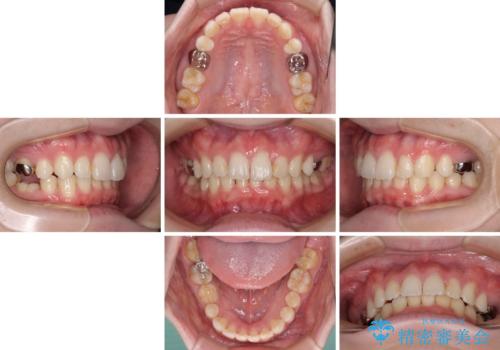

- 咬み合わせと前歯のデコボコを気にして来院された患者様です。

前から5番目の永久歯が3本欠損しており、乳歯が残存している状態でしたが、インビザラインでも十分に対応可能と判断し、インビザラインにて矯正治療を行うこととしました。

右下の残存している乳歯は萌出しきれておらず、全く咬み合っていない状態であり、インビザラインにて移動できない可能性があるため、ワイヤー矯正の併用も念頭に置いて治療を開始しました。

萌出が不十分な歯はインビザラインで引き出すことができないため、ワイヤー装置などの併用が必須となります。

今回は部分的にワイヤー矯正を用いましたが、右下の乳歯は全く動かなかったため、抜歯をした上でインプラントを埋入し、オールセラミッククラウンにて補綴治療を行いました。